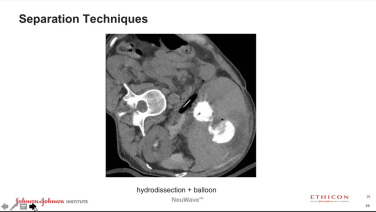

Ablação por micro-ondas do fígado e do rim, com o Dr. Khashayar Farsad